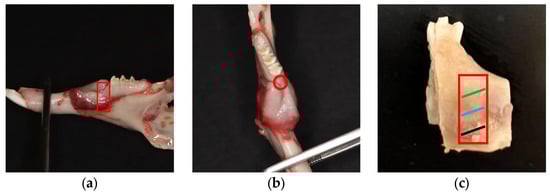

4.3. Surgical Procedure

4.4. Sample Collection